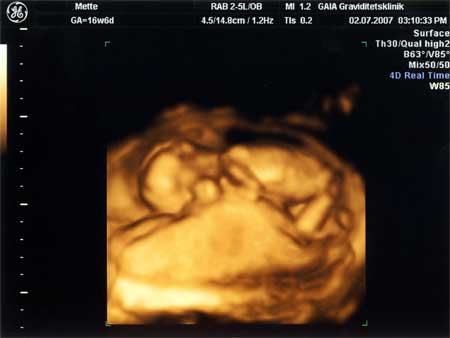

3D scanning – se baby i maven under graviditeten

3d scanning uge 16

3d scanning – uge 16

uge 16+0

Jeg ligger og putter mig op ad "madpakken"